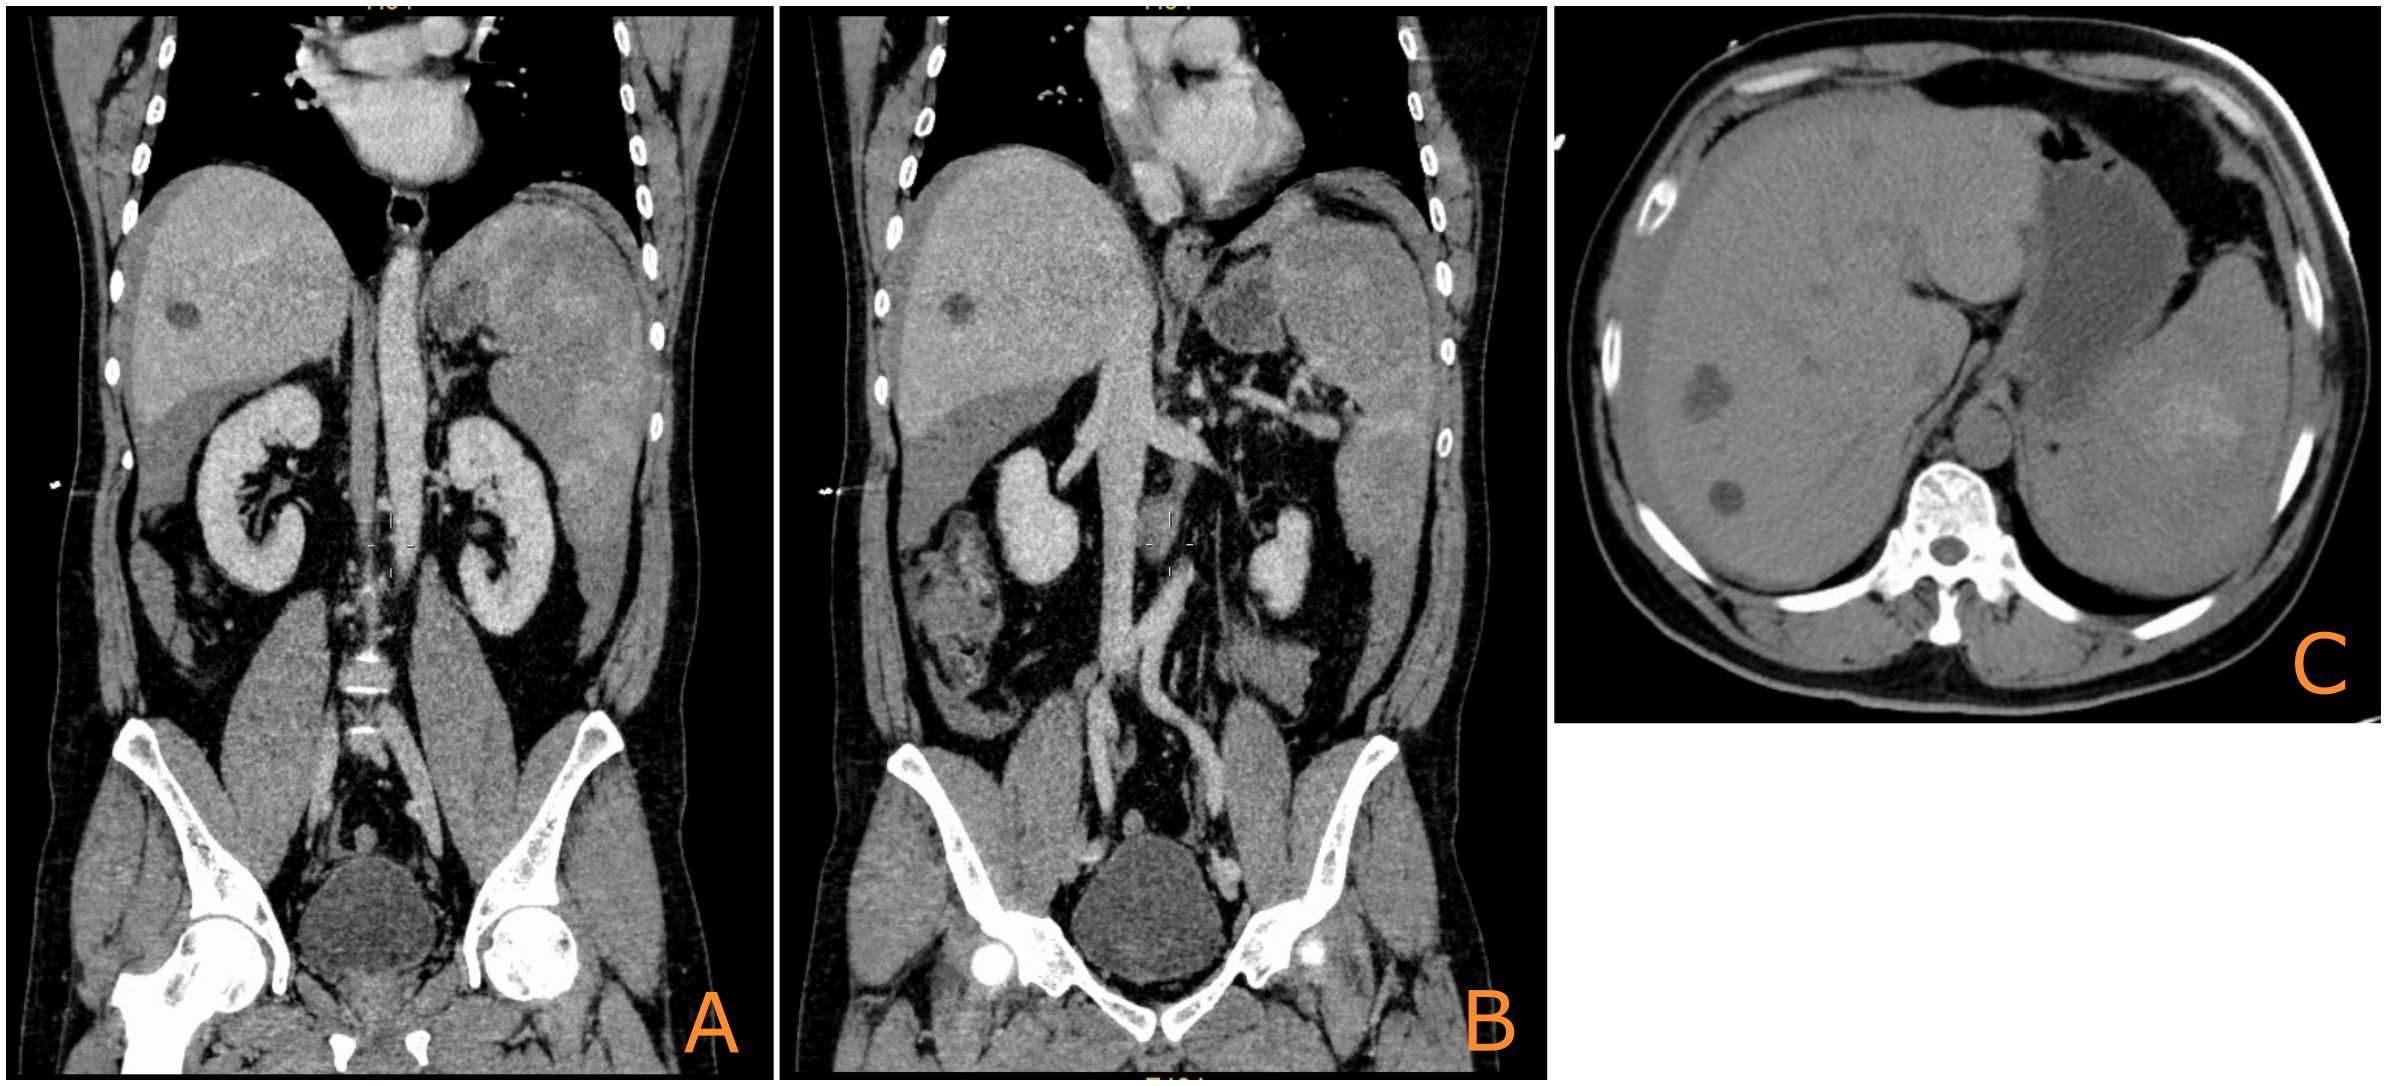

Background Primary splenic angiosarcoma (PSA) is an exceedingly rare and aggressive malignancy with a poor prognosis. This report aims to present a rare case of PSA that progressed to fatal hepatic rupture due to rapid metastatic spread following splenectomy and adjuvant therapy, a review of the relevant literature is also provided to discuss the diagnostic and therapeutic challenges associated with this condition. Case Presentation A 52-year-old male patient presented with acute abdominal pain and hypovolemic shock. Imaging revealed splenic rupture with hemoperitoneum. An emergency splenectomy was performed, and histopathological examination confirmed the diagnosis of angiosarcoma. The patient received postoperative chemotherapy (liposomal paclitaxel) and subsequent targeted therapy (sunitinib). However, rapid hepatic metastasis occurred, leading to spontaneous hepatic rupture and death six months after the initial diagnosis. Conclusion The condition poses a diagnostic and therapeutic challenge due to its nonspecific presentation and high aggressiveness. Early splenectomy remains the prevailing standard of care. This case demonstrates the potential inefficacy of sunitinib against PSA derived hepatic metastases and emphasizes the critical importance of early diagnosis and intervention before splenic rupture occurs. The potential for combination therapies, including immunotherapy, to represent future investigative avenues is a promising area for future research.